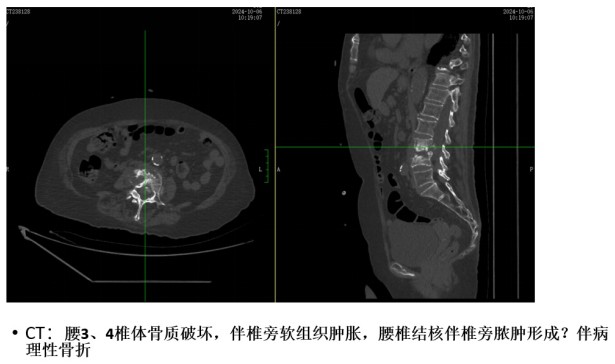

為解決老人病痛,脊柱外科錢軍博士團(tuán)隊(duì)對(duì)其進(jìn)行了詳細(xì)的查體以及全面細(xì)致的評(píng)估,診斷為L3、4脊柱結(jié)核伴病理性骨折、椎旁膿腫,患者腰部疼痛癥狀逐漸加重,病灶已經(jīng)壓迫神經(jīng)引起了截癱。